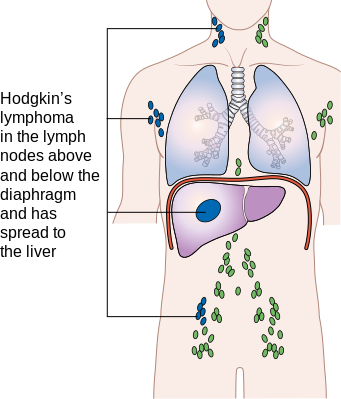

Estadiamento Ann-Arbor modificado: doença localizada - estágio 1

Uma cadeia ou estrutura linfoide (baço, timo).

Estadiamento Ann-Arbor modificado: doença localizada - estágio 2

≥ 2 cadeias no mesmo lado do diafragma.

Estadiamento Ann-Arbor modificado: doença avançada - estágio 3

Ambos os lados do diafragma.

III1: andar superior.

III2: andar inferior.

Estadiamento Ann-Arbor modificado: doença avançada - estágio 4

Acometimento extranodal. Distante (fígado, MO).

Paciente com linfoma em duas cadeias linfonodais, também acometendo o fígado.

Qual o estágio?

ESTÁGIO 4

Acometimento extranodal extenso (fígado, MO) não por extensão direta.